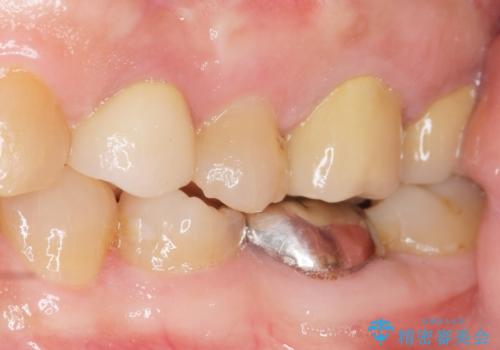

「今まで何回治療しても治らなった膿が出なくなった!」と喜んで下さいました。

銀座しらゆり歯科の林院長の精密根管治療は素晴らしく、難易度の高いケースも治して下さり患者様の満足度も非常に高いため、紹介した私も嬉しくなります。

クラウンの種類:メタルボンドクラウン エコノミー